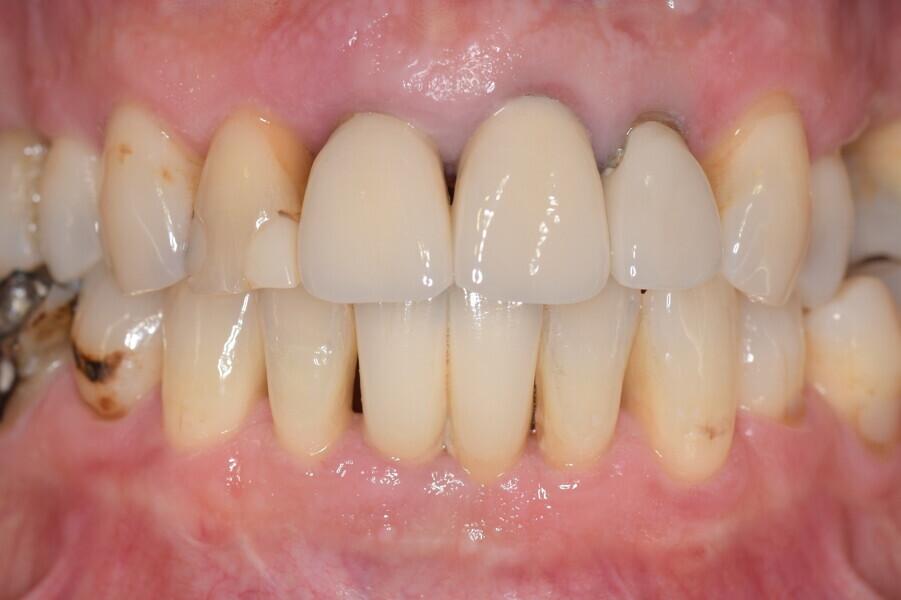

A 62-year-old male patient was referred to my practice for implant planning and treatment in the maxillary anterior region. The teeth in the maxillary anterior region had all undergone endodontic therapy, and teeth #11-22 had received crowns owing to an accident that had occurred 30 years before. The patient reported pain and was conscious that tooth #21 was mobile (Figs. 1a & b).

Fig. 1b: Initial situation.